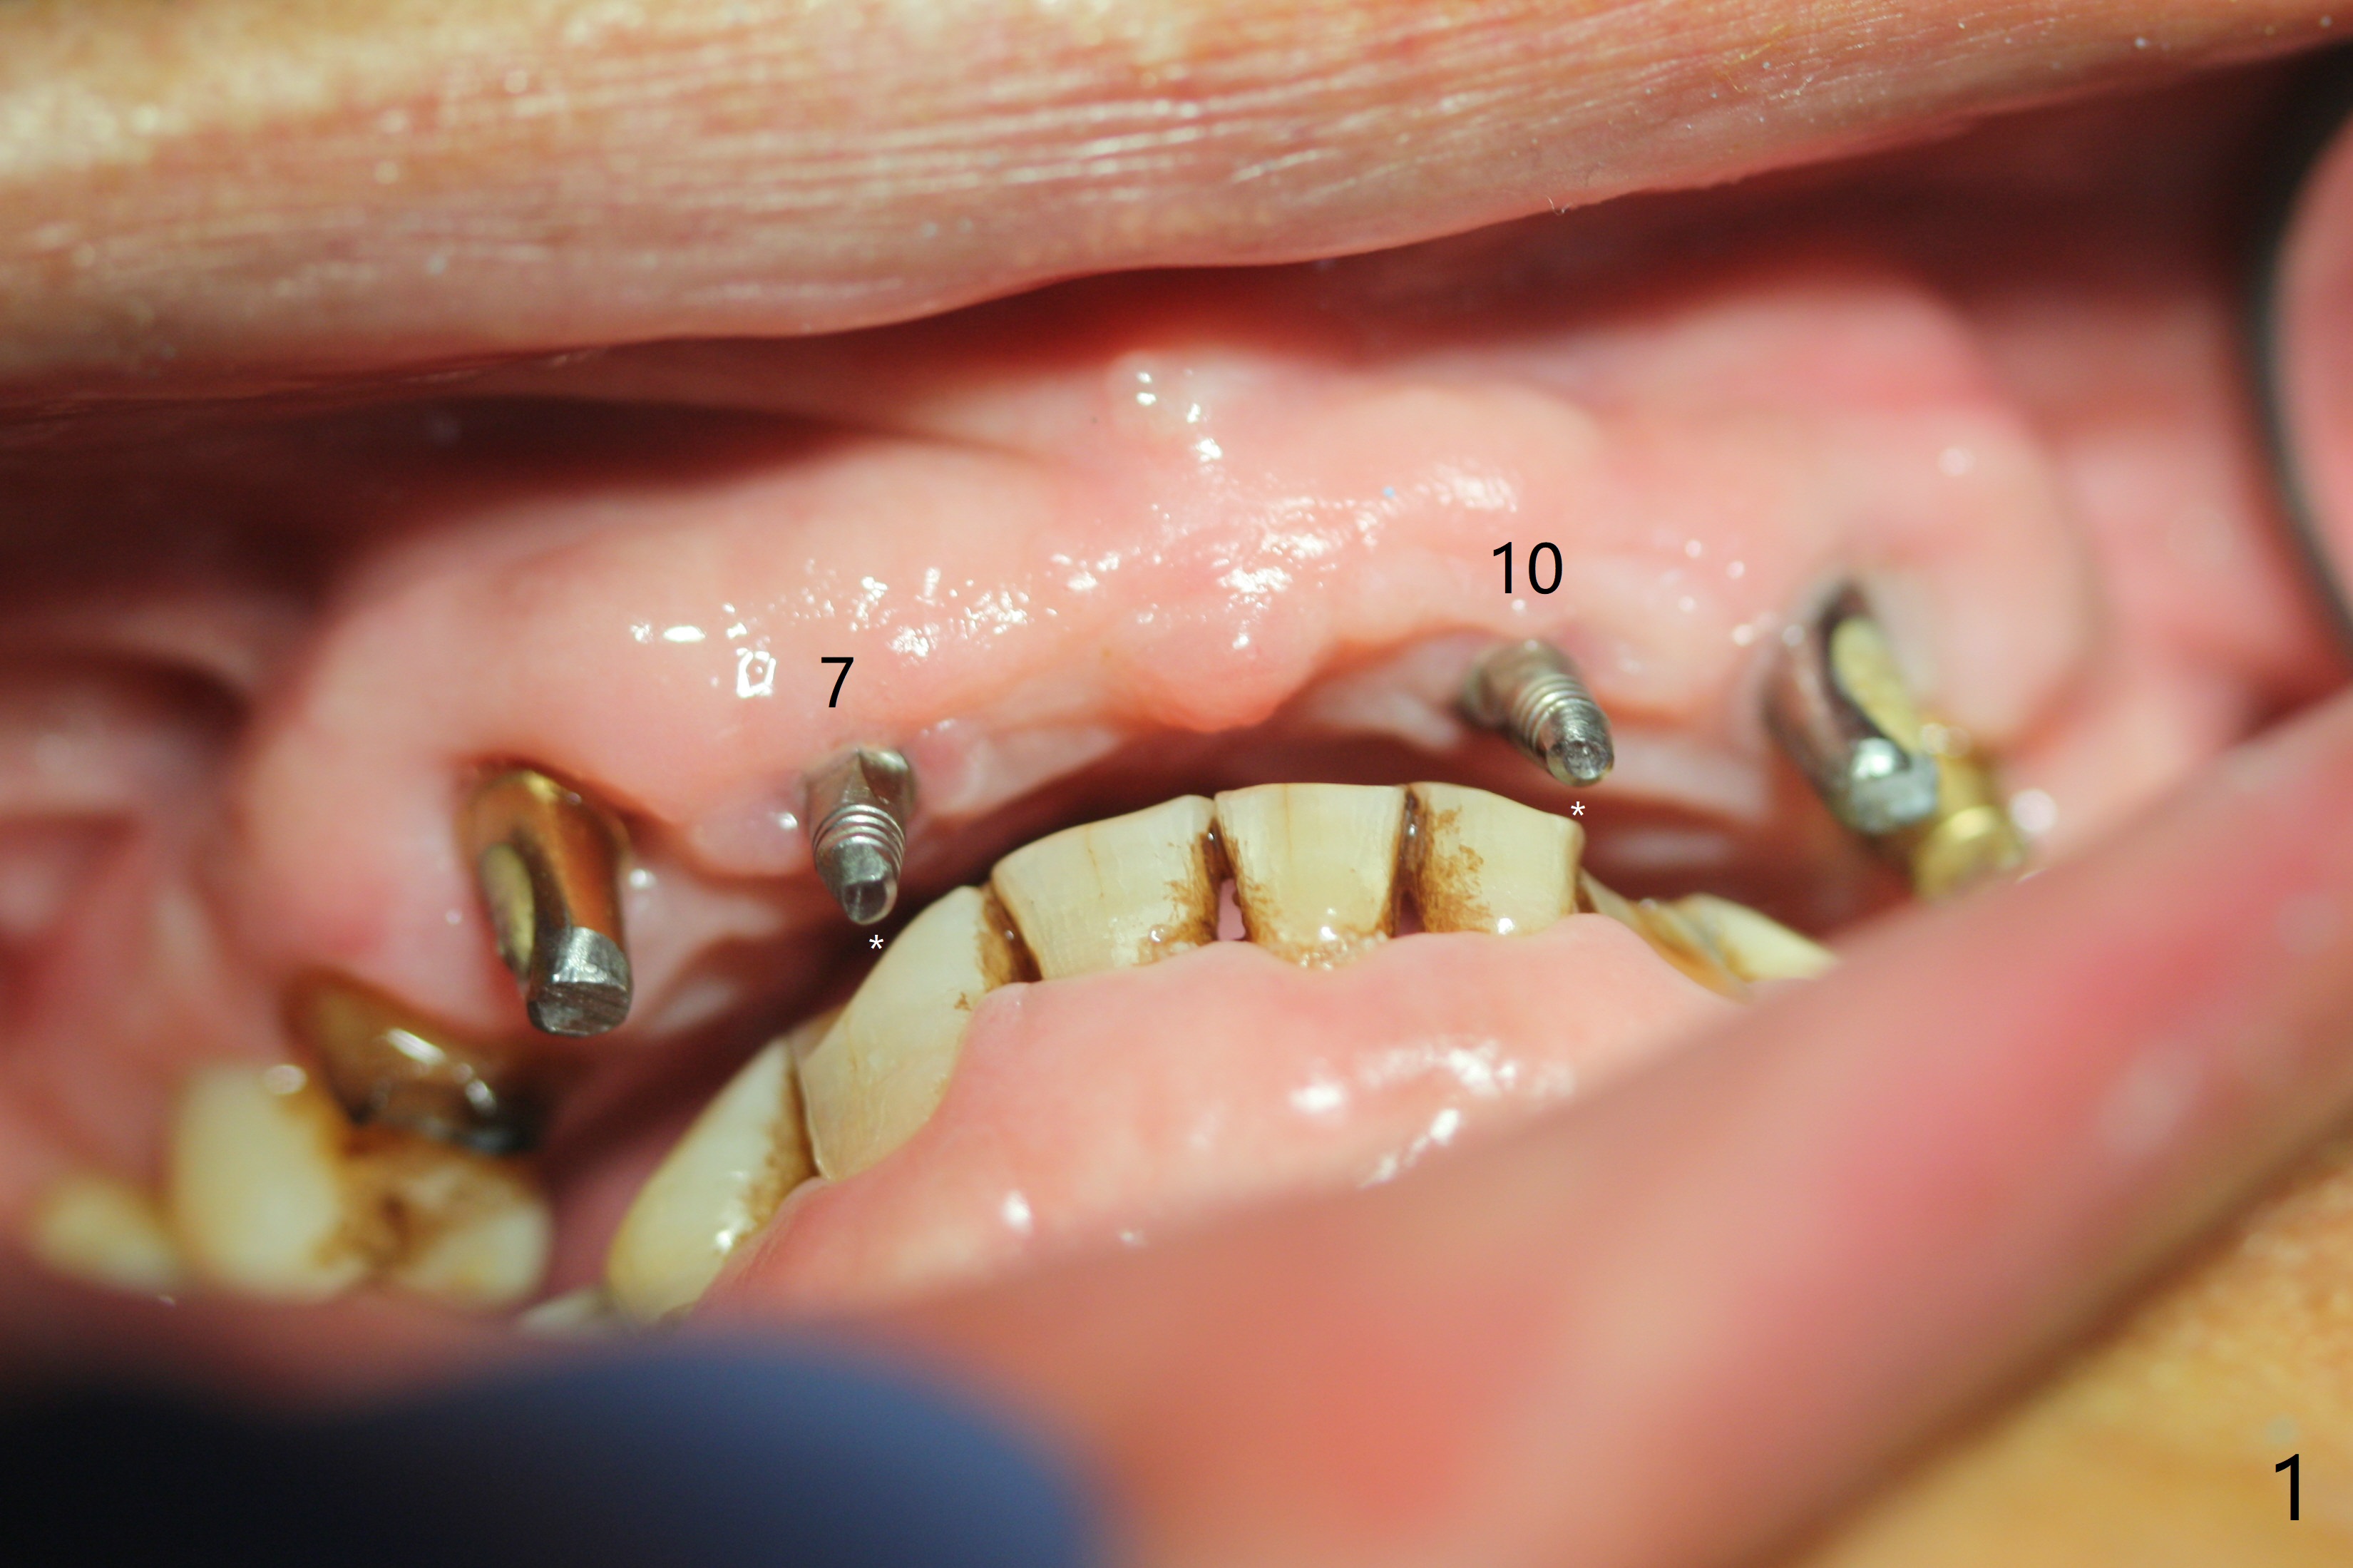

To have enough clearance for the splinted provisional at #6-12 (Fig.1 *), composite has been placed in the posterior teeth (bilateral, *, Fig.2). When the composite is removed, there is no clearance between the implants/abutments of #7 or 10 (Fig.3). Incision is made with removal of the 1-piece implant at #7; there is enough bone to move the osteotomy buccal (Fig.4 arrowhead). When the same implant is placed buccal (Fig.5), there is sufficient clearance for restoration (Fig.6 *), while there is still enough buccal bone left (Fig.7). When the patient returns 5.5 (for #7 and 10)/6.5 (#6,11,12) months postop, his chief complaint is tenderness lingual to #11. In fact, the abutment screw is loose at #11, while the implant at #10 has mobility (Fig.8), which is related to loss of the posterior stops (*) due to wear. There is slight bone loss mesial to #10 implant 5.5 months postop (Fig.10, as compared Fig.9). CBCT taken 5.5/6.5 months postop shows no bone loss (Fig.11-15). The 3x14 mm 1-piece implant at #10 is mobile 9 months postop and is removed and replaced by a 3.5x13 mm 2-piece one with slightly buccal osteotomy (Fig.16). PAs are taken prior to impression (Fig.17,18). The abutment at #12 is loose (<). More composite needs to be added to the occlusal surface of the upper posterior teeth. Finally the patient agrees to have crowns for the upper posterior teeth.